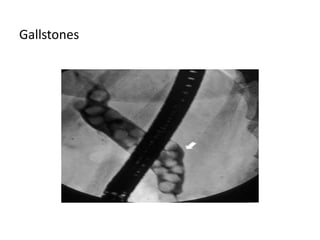

Pathologies

Biliary stones

Gallstones